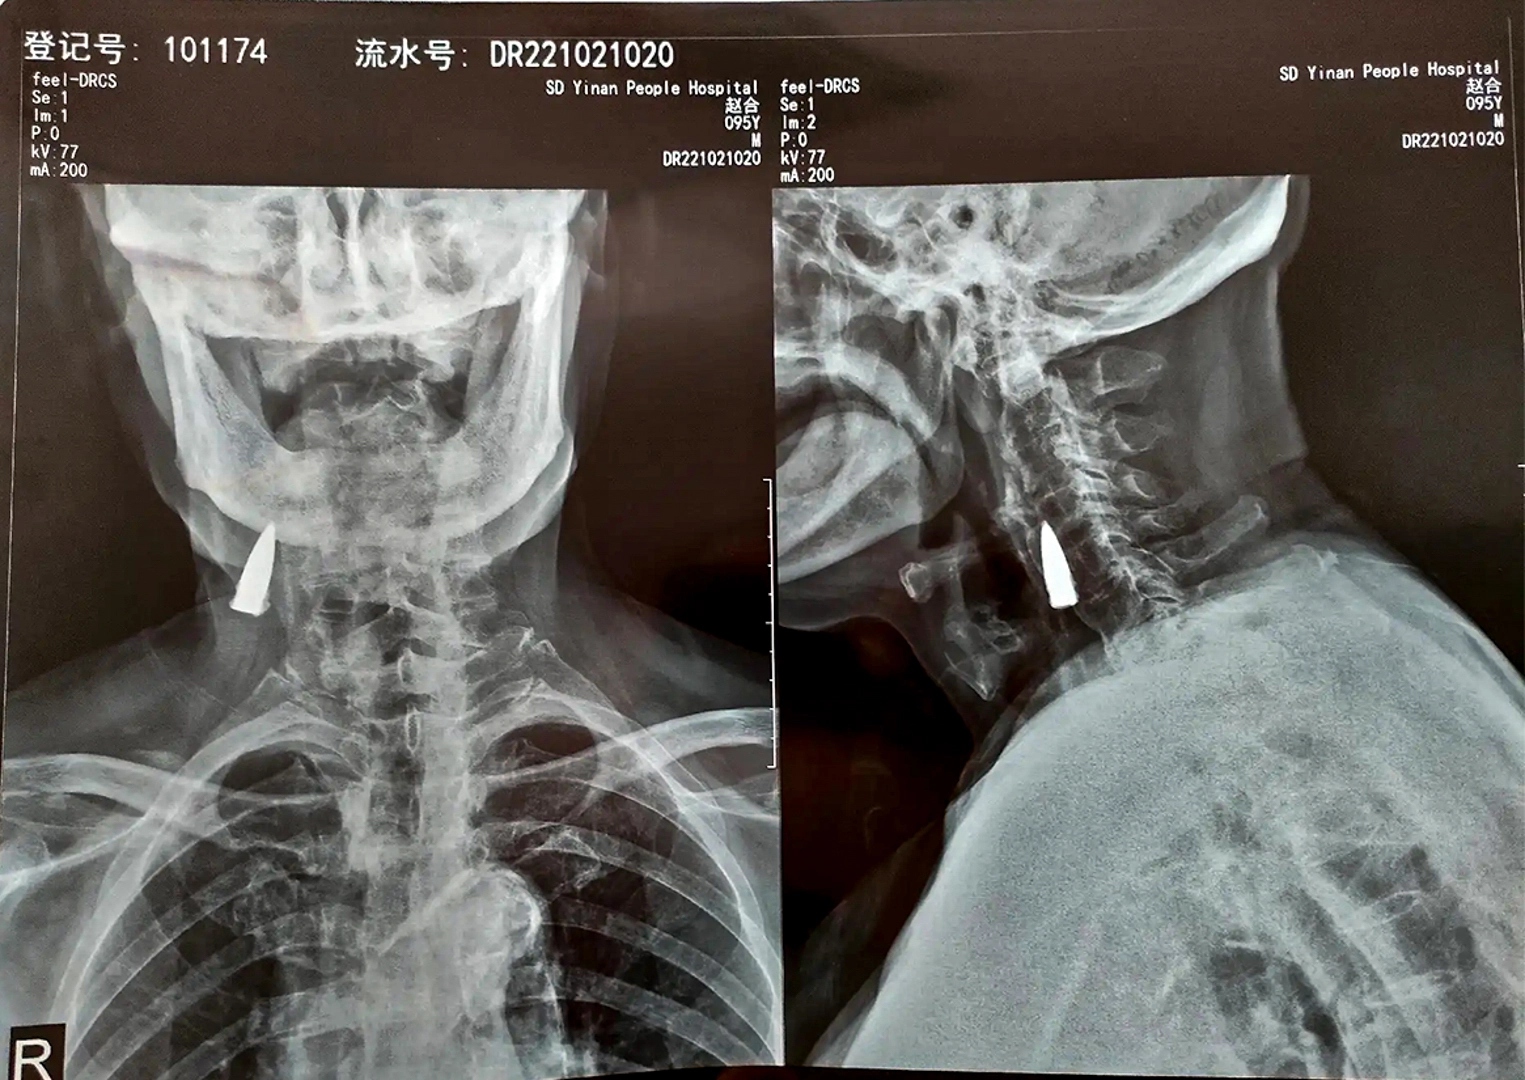

Sin siquiera darse cuenta y después de 80 años cuando se sometió a una radiografía en el Hospital de Shandong, en China, descubrió que tenía una bala incrustada en su cuello.

Asimismo, no se sabe con exactitud cómo es que la bala llegó hasta su cuello, la cual está cercana a vasos sanguíneos, justo debajo de la mandíbula.